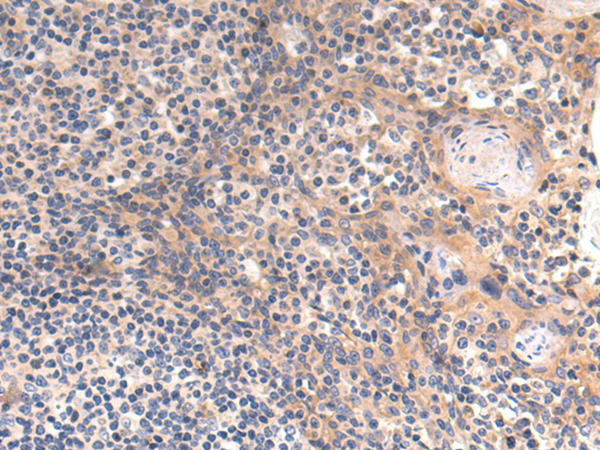

分类: 科研抗体货号: P10600别名: FAKTS; URLC9; hFLEG1应用: IHC反应种属: Human